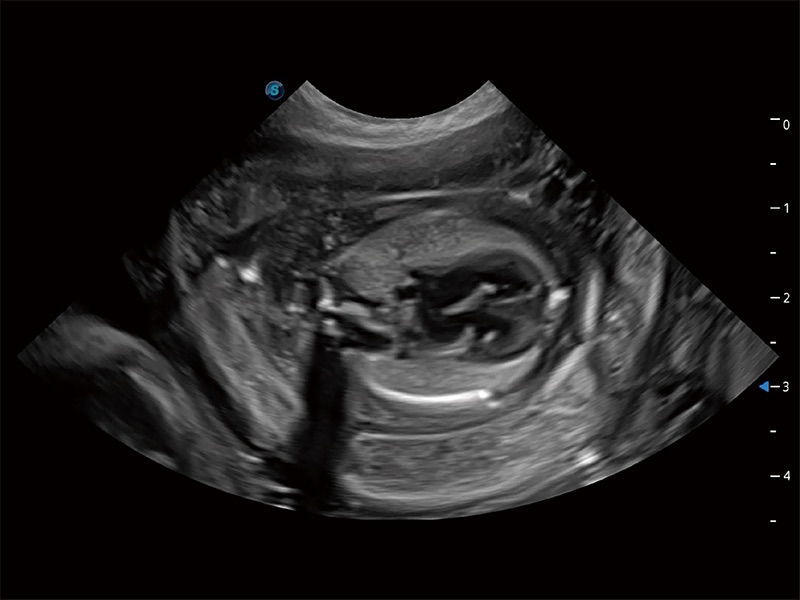

动物是人类最亲密的朋友和最值得信赖的伙伴。米兰官方网站也一直致力于探索动物专用的超声影像解决方案。全新推出的ProPet系列,是米兰官方网站在动物超声影像智能化、专业化、精准化的一次跨越式革新。动物不能用言语来表述自己的不适,通过超声影像,ProPet系列搭建了动物医生与不同物种沟通的“桥梁”,为动物医生注入了“治愈之力”。 ProPet 80 是米兰官方网站匠心打造的一款高端动物专用彩超,采用性能卓越的全新硬件架构,极大提升超声系统的运行效率和数据处理能力,帮助动物医生从容应对日益增多的挑战性病例和日益多样化的临床需求。

高性能和先进的临床应用工具可以为动物医生提供临床信心。ProPet 80 搭载了先进的腹部和浅表应用工具,帮助医生在日常临床实践中发挥前所未有的作用。

ProPet 80 全新的动物超声智能软件和丰富的探头群,为动物医生提供了高清晰度和精细分辨率的图像,无论在宠物、马科、畜牧还是实验室动物等应用中都可以轻松应对,为您的日常工作带来满意的体验。